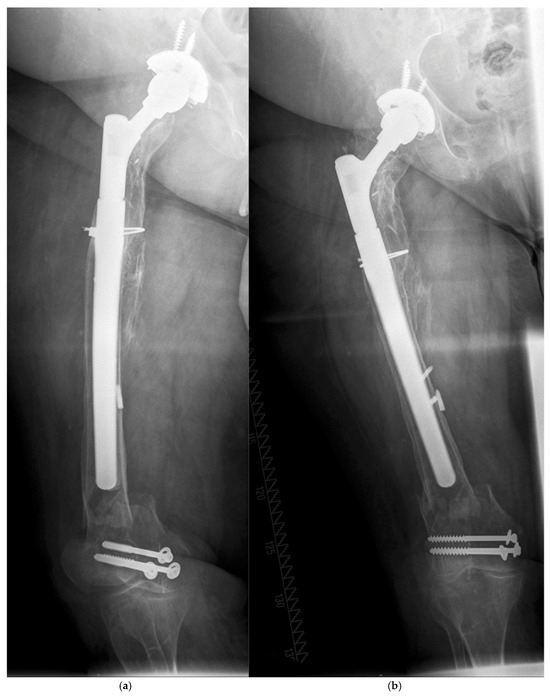

| 77, f. | TSR | 4 | TG | 20.8 | y | 4.2 | C | O (ORIF by Plate) | 290/14 |

| 68, f. | AL | 2B | TG | 22.5 | n | 0.8 | C | O (ORIF by Plate, Liss ©) | 250/18 |

| 73 +, f. | AL | 3B | TG | 34.4 | n | 8.6 | C | O (MIS by Plate, VA ©) | 290/21 |

| 75, f. | AL | 2B | TG | 25.9 | n | 9.8 | C | O (ORIF by Plate, VA ©) | 250/19 |

| 76, f. | AL | 2A | TG | 31.8 | n | 0.1 | B1 | O (ORIF by Plate, Liss ©) | 240/22 |